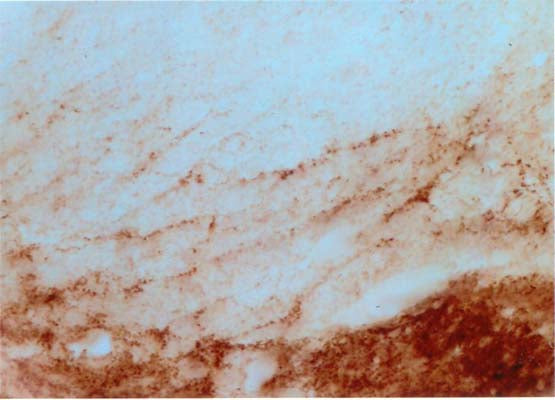

Anti-Beta-synuclein Antibody

Our Anti-Beta-synuclein sheep polyclonal primary antibody detects human and rat Beta-synuclein, and is whole serum. It is validated for use in IHC-Frozen.

IHC: 1:3000-1:8000